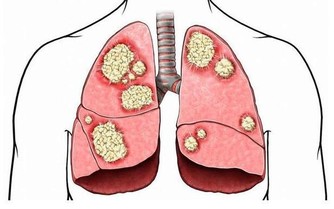

高血壓誘發腎衰竭,臨床大多表現在代謝產物瀦留,水分,電解質,酸鹼代謝物失衡,繼而導致腎小球過濾功能下降,以及良性甚至惡性的小動脈腎硬化。如果不及時進行調整,後續發展成為慢性腎衰竭的風險就會增加。

換句話說,我們可以將腎衰竭看做是高血壓惡化的並發症的一種。而拒絕正常的服藥流程,就相當於無限擴大了高血壓惡化的風險。

而長期存在漏藥,少服一類地打亂用藥規律的行為,就相當於身體存在長時間的血壓波動,尤其對於腎臟來說,入球小動脈以及小葉間動脈發生炎症的概率增加,出現慢性腎病甚至腎衰竭的概率也會無限增大,還請一定要注意。